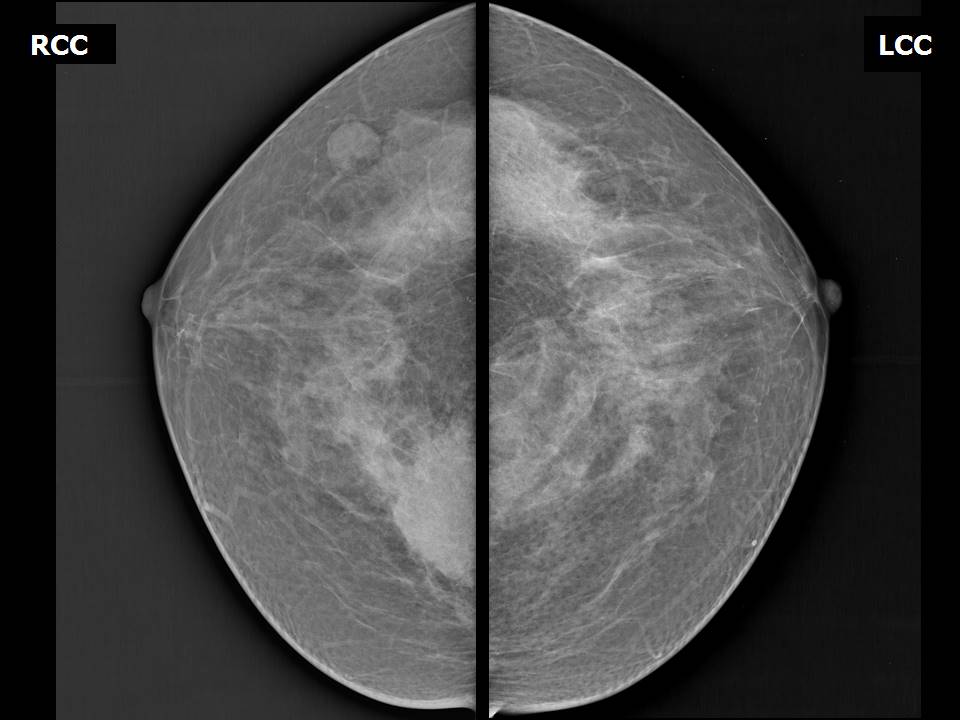

Аномалии молочной железы: медицинские примеры и визуализация

Раздел: Мудрость в деталях